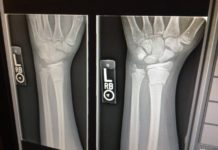

Nuovo infortunio al ginocchio per Milik: è davvero solo sfortuna?

In questa settimana è rimbalzata un po' ovunque la notizia del nuovo infortunio per l'attaccante del Napoli Arek Milik, classe 1994, rientrato da pochi...

Tesserati attenzione! Apre nell’area fiorentina il servizio di traumatologia dello sport

FIRENZE - Attivo da mercoledì 4 ottobre, nell’area fiorentina, il servizio di traumatologia dello sport dedicato agli atleti agonisti, sia professionisti che dilettanti tesserati...